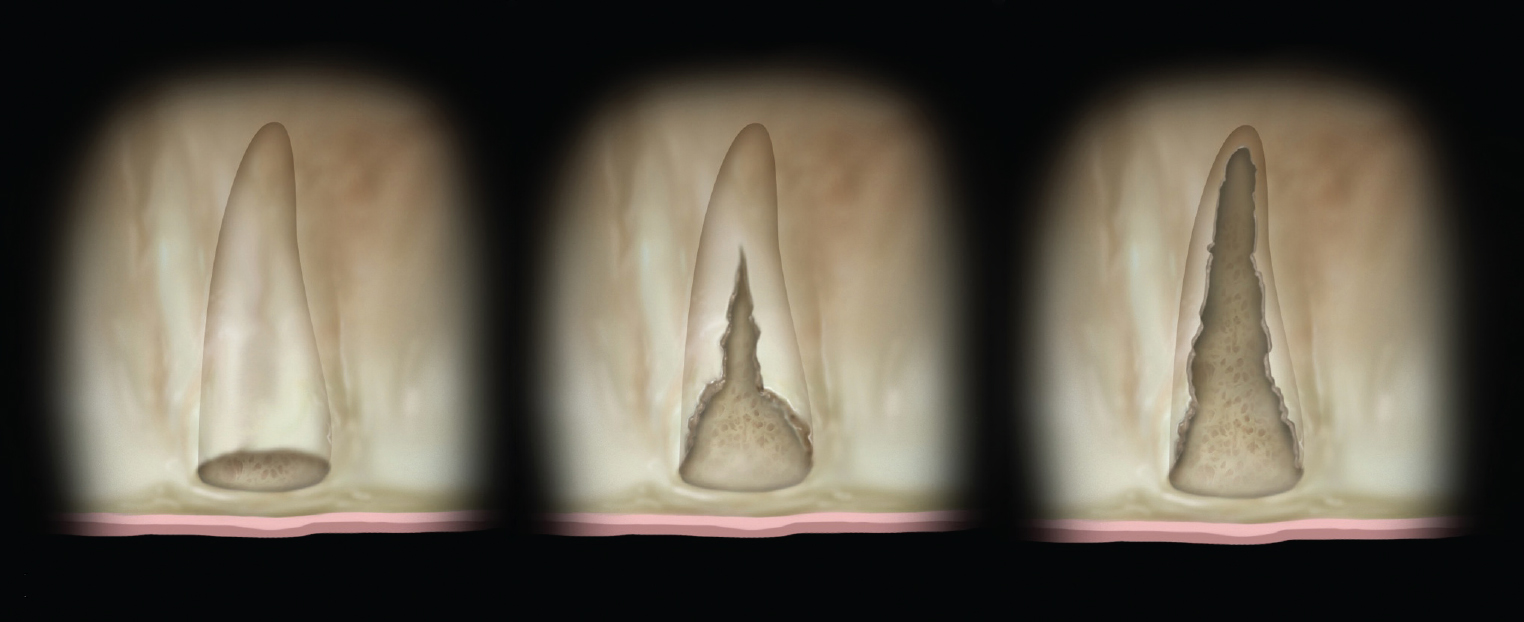

Figure 3

(Left) Grade I socket with an intact buccal plate demonstrating less than 25% bone loss; (Center) Grade II socket showing  ssure, dehiscence, and approximately 50% buccal plate loss; (Right) Grade III socket with more than 50% buccal plate loss.